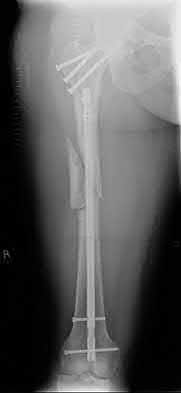

3. # Which of the following is not an appropriate implant for treatment of the fracture seen in Figure A?

5. Sliding hip screw Corrent answer: 5

The image shows a reverse obliquity intertrochanteric hip fracture.

According to the referenced article by Haidukewych et al, unstable peritrochanteric hip fractures have a worse outcome (failed in 9/16 cases) if treated with a sliding hip screw. Two additional factors that were found to have a strong correlation with postoperative failure (nonunion, loss of reduction) were poor reduction and poor implant placement. In this study, fixed angle devices were superior. Intramedullary fixation has the added advantage of a shorter lever arm and less potential for fracture collapse and limb shortening.

The IMN also acts as a medial buttress.

According to Sanders et al, the dynamic condylar screw (DCS) can also be used in subtrochanteric models, but should not be used if extensive comminution is seen, as they reported a high failure rate with DCS in these fractures if highly comminuted. They report a 77% overall union rate with this device.